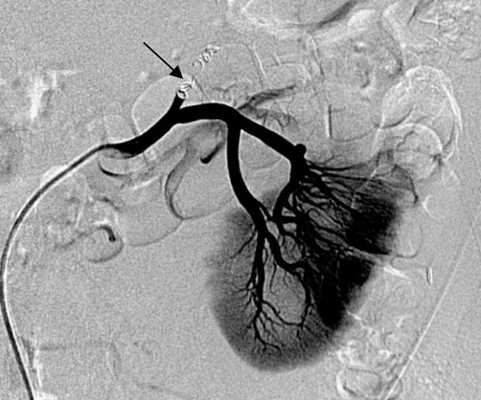

Проведено лечение: 1 курс иммунохимиотерапии без особого эффекта. Следующим этапом провели эмболизацию опухоли правой почки и селективную эмболизацию опухоли нижнего полюса левой почки (рис. 1, 2) с последующей нефрэктомией правой почки (рис. 3) с целью циторедукции с последующей химиоиммунотерапией. Пациентка в период 2010-2012 гг. получила таргетную терапию препаратом Сорафениб по 400 мг 2 раза в сутки в течение двух лет, далее у нее развилась непереносимая токсичность препарата, и лечение было остановлено. В настоящее время при контрольном обследовании данных за прогрессирование не выявлено, на контрольной ангиографии левой почки опухоль в динамике без признаков реваскуляризации и роста (рис. 4).

Рисунок 4. Контрольная ангиография левой почки через шесть месяцев (А), два (Б) и десять (В) лет после комбинированного лечения пациентки К.

Figure 4. Control angiography of the left kidney at six months (A), two ( Б ) and ten (В) years after the combined treatment of patient K.